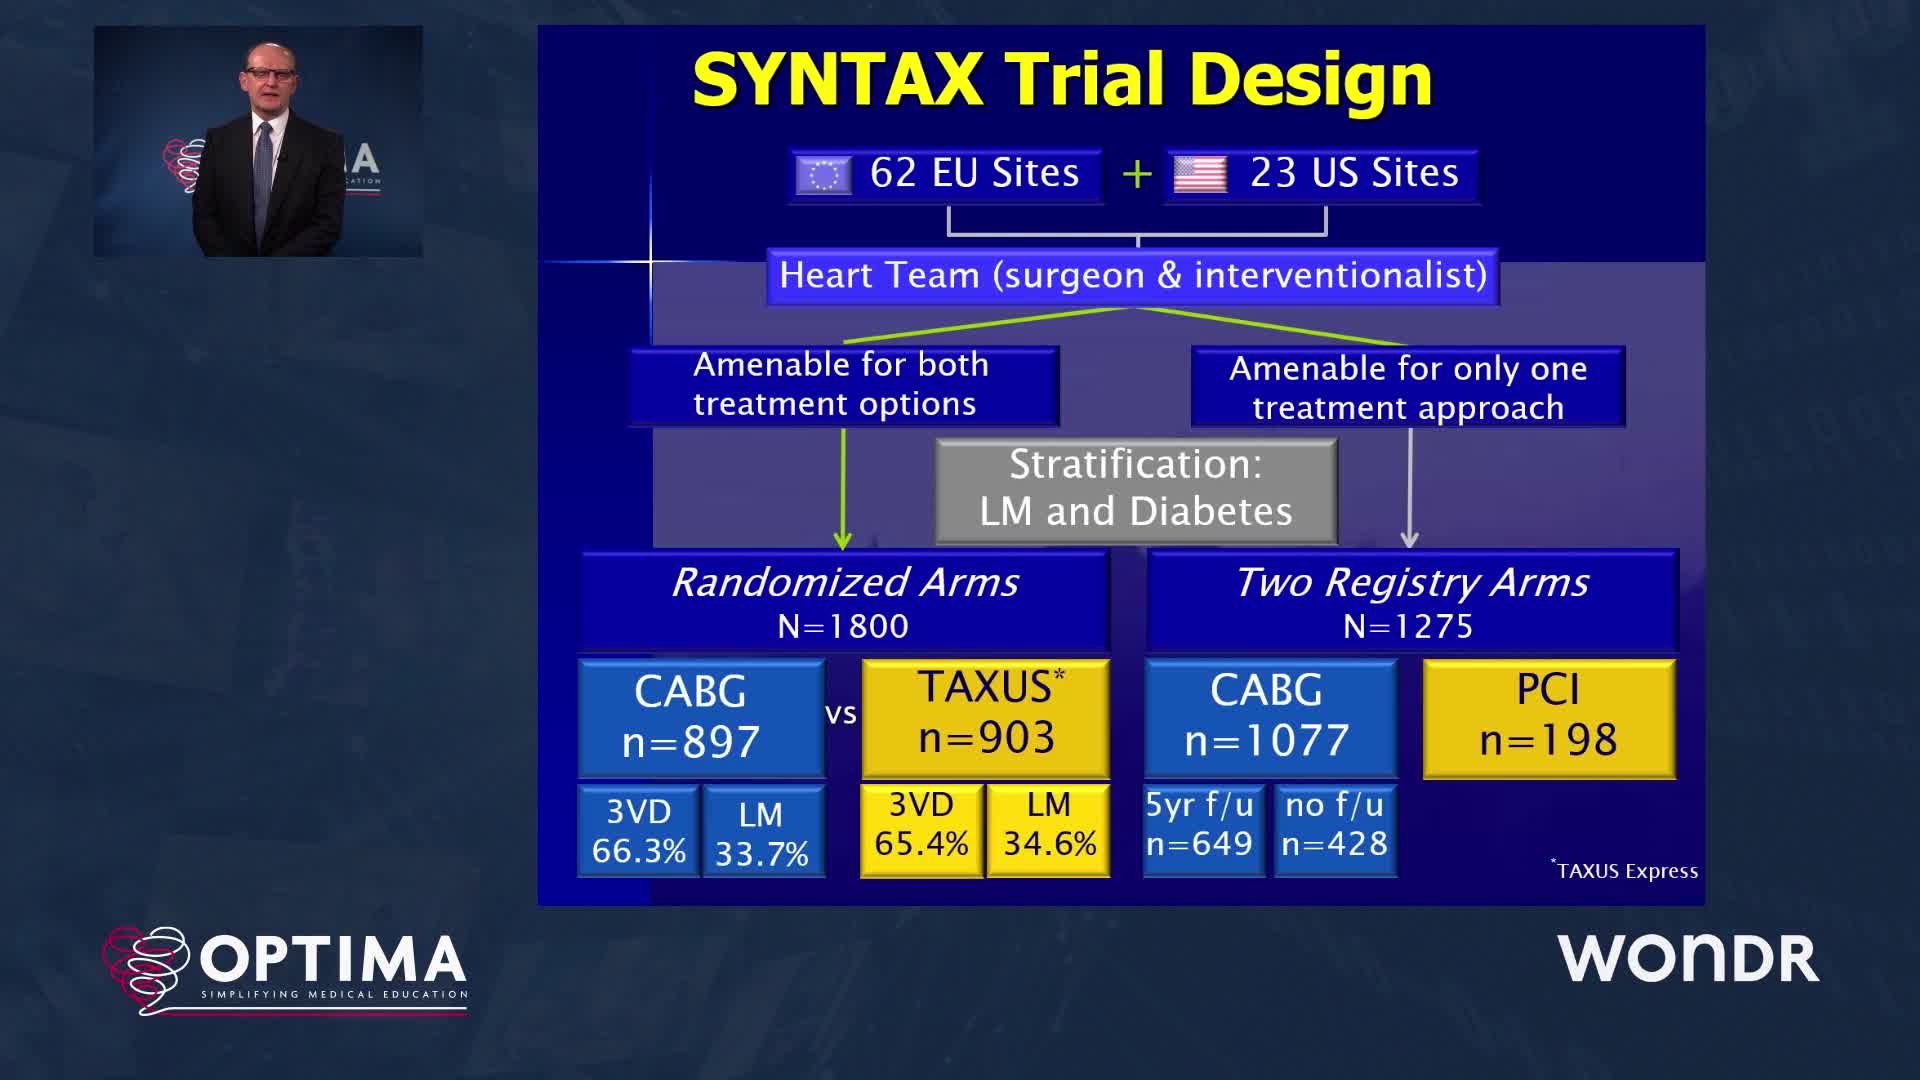

Addressing the controversy of LM revascularisation PCI head-on by first providing the statistical weapons to...